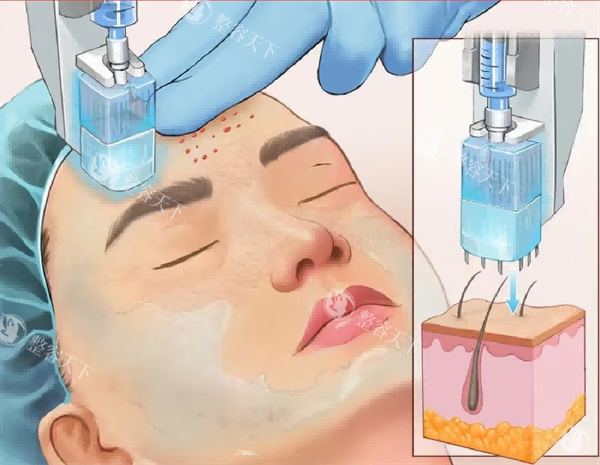

薇琳医院在 peek 颅骨修补时,不仅看重修补的结果,还特别在意患者术后的修养和美观度。

他们采用的是小创口技术,手术伤口小,修养起来比较快。术后还会有专门的护理团队跟进,帮助患者更快地修养正常生活。

另外,医生在设计修补方案时,会充分考虑患者的面部轮廓,让修补后的头部线条更流畅,从外观上几乎看不出手术痕迹。